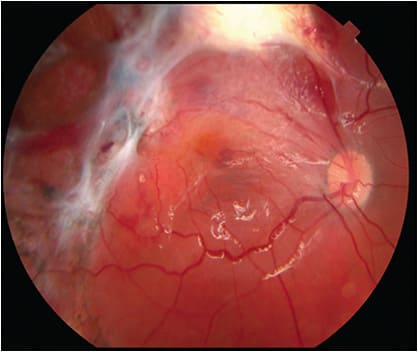

Traumatic endophthalmitis (TE; Figure 5) occurs in 0% to 30% of open-globe injuries.9,22,52-54 Open-globe injuries with concurrent endophthalmitis require emergent surgical closure of the globe with injection of intravitreal antibiotics, systemic antibiotics, and, if possible, PPV. Most eyes with TE develop infection within a few days after open-globe injury. Patients with fungal infection may present with a more protracted time course. Any patient with open-globe injury who presents with endophthalmitis should undergo special studies (eg, CT scan) if a retained IOFB is a possibility based on the history and circumstances of the injury. The microbiological spectrum of TE differs from that of postoperative endophthalmitis with greater prevalence of virulent organisms such as Bacillus species and S. aureus.55,56 The patient’s condition can worsen within hours with many patients so afflicted going on to have NLP. Almost all TE cases will require PPV with intravitreal antibiotics emergently. If the infection is very early and mild (20/30 or better view of the retina due to vitritis) or if there is a delay in performing PPV due to unavoidable circumstances as noted above, one should consider bedside intravitreal antibiotic administration as initial therapy.